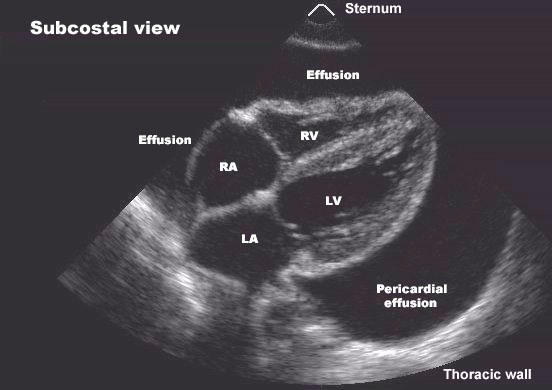

Ecocardiograma

Quando há suspeita de Derrame Pericárdico, este é o melhor exame para fazer o diagnóstico, pois o excesso de líquido à volta do coração, geralmente, é facilmente visto, confirmando o diagnóstico.

Depois da conclusão do diagnóstico, o médico avalia o tamanho e a gravidade do Derrame. Na maioria dos casos, o Derrame Pericárdico é pequeno e não causa problemas graves. Em contraste, grandes Derrames podem comprimir o coração e prejudicar a sua capacidade de bombear sangue. Esta patologia, chamada Tamponamento Cardíaco, é um resultado potencialmente fatal de um Derrame Pericárdico.